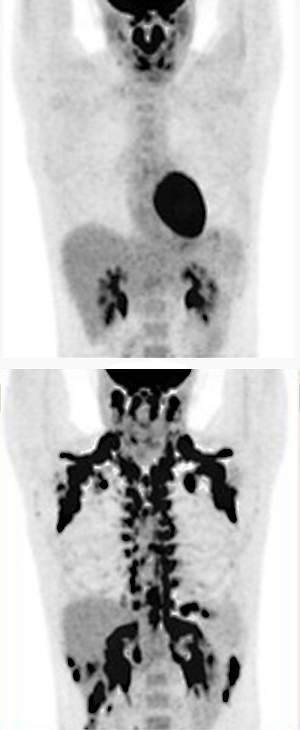

Several hours after taking the drug or placebo, participants received infusions of a traceable form of glucose. The researchers found that participants had increased glucose uptake in several tissues, including brown fat, after taking the drug mirabegron. Using PET and CT scanning, the scientists found that the drug increased brown fat metabolic activity. Resting metabolic rate also rose by an average of 203 calories per day. The increase in metabolic rate was associated with the increase in brown fat activity.